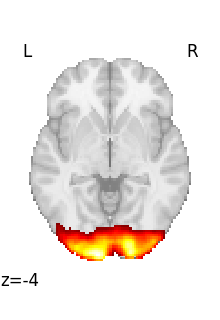

Visualizing a 3D file¶

The file contains a 3D volume, we can easily visualize it as a statistical map:

from nilearn import plotting

plotting.plot_stat_map(tmap_filename)

<nilearn.plotting.displays._slicers.OrthoSlicer object at 0x7f3bc6a0ce60>

Visualizing works better with a threshold

plotting.plot_stat_map(tmap_filename, threshold=3)

<nilearn.plotting.displays._slicers.OrthoSlicer object at 0x7f3bc69e1d00>